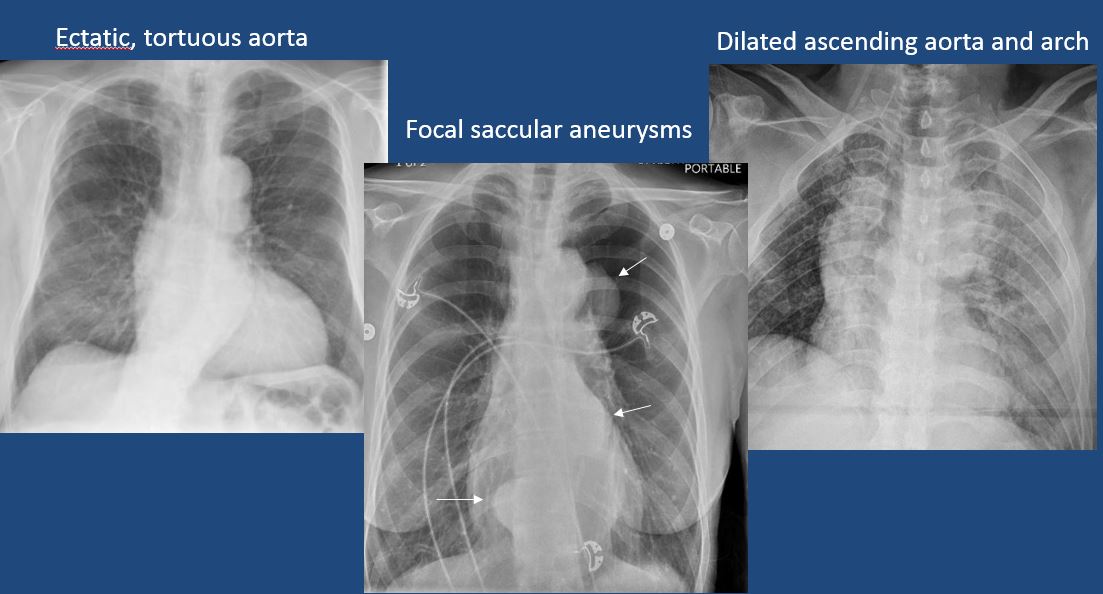

The aorta is dilated, tortuous, ectatic, calcified, or there is a focal contour abnormality. [Yes/No]